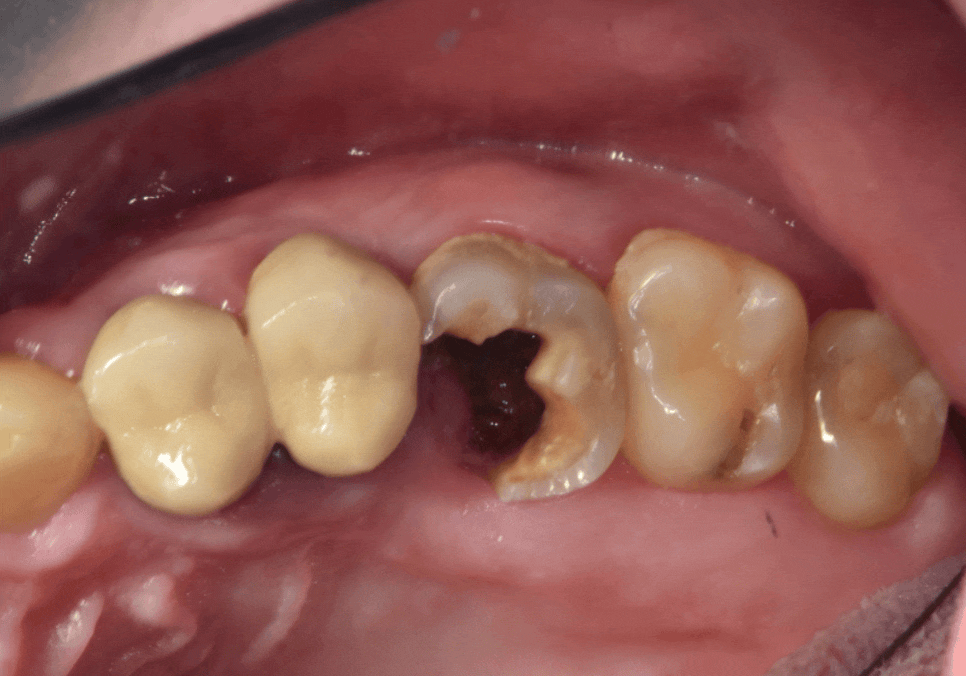

입안을 보니 이미 치아가 충치로 인해

많이 삭아 있었습니다.

방사선 사진상으로는 상태가 더 심각했는데요.

보이는 것보다 충치가 훨씬 깊게 파고들어,

마치 겉면만 간신히 남고

속은 텅~비어버린 상태였어요.